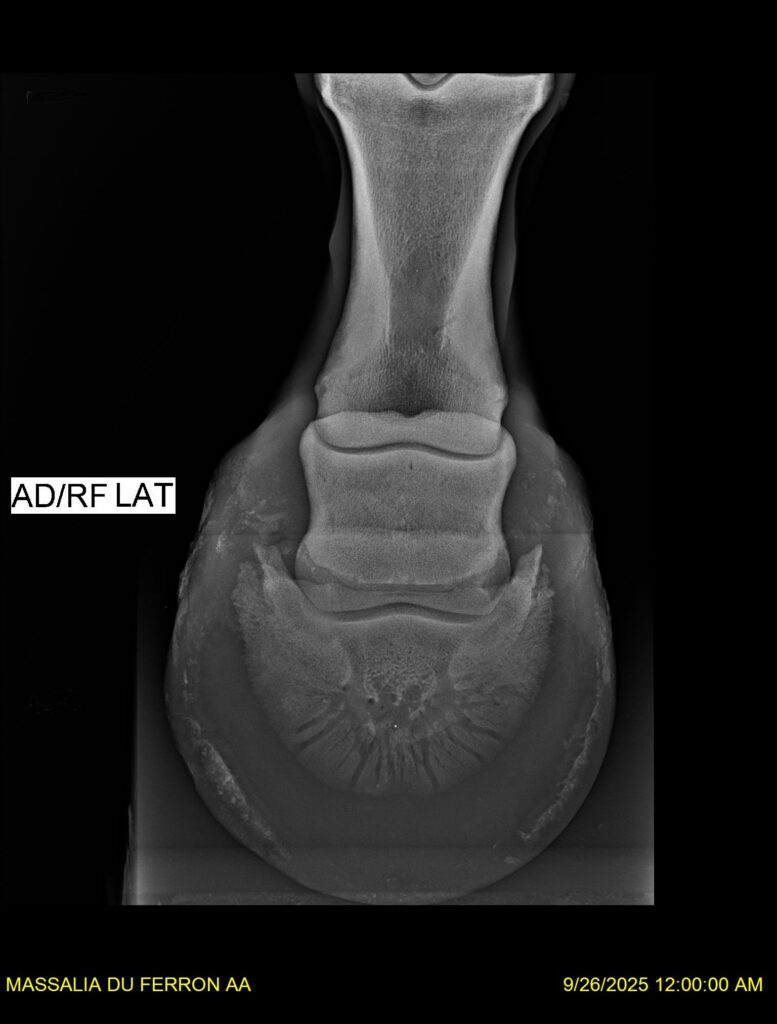

MASSALIA DU FERRON, jument qui prendra 4 ans par PRESTIGE KALONE x TRESOR DU RENOM. Un mental en or et un véritable sens de la barre ! Facile d’accès ! Bonne énergie et bons moyens. Souche moderne et très intéressante. Transport OK, maréchalerie OK, santé RAS, Bilan clichés radios OK.

RADIOS et COMPTE RENDU